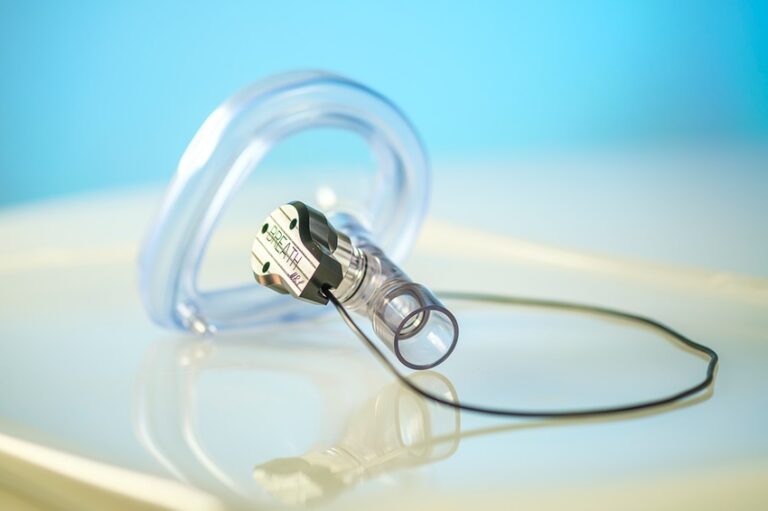

Lees meerMedtronic mag oplaadbare spinal cord stimulator in VS op markt brengen

(PARTNER NIEUWS)

De Inceptiv oplaadbare spinal cord stimulator (CSC) van Medtronic is in de Verenigde Staten (VS) door de Food and Drug...

De Inceptiv oplaadbare spinal cord stimulator (CSC) van Medtronic is in de Verenigde Staten (VS) door de Food and Drug Administration (FDA) goedgekeurd voor de behandeling van chronische pijn. Het...

Medisch & Zorg / 20-05-2024